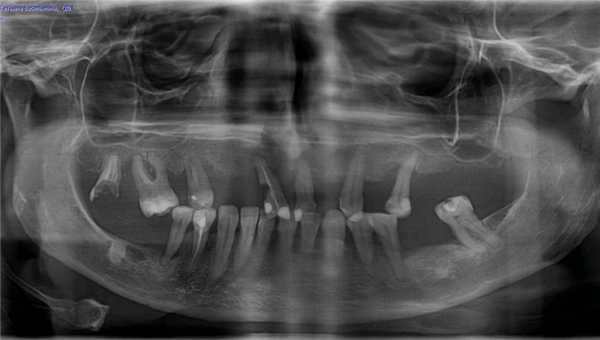

По результатам рентгендиагностики (ортопантомогафии) выявлено неравномерное разрушение половины костной межзубной перегородки по смешенному типу (горизонтальное и вертикальное), а также кистогранулёмы и значительное разрушение в области трёх жевательных зубов (26, 27 и 47).

Хронический генерализованный пародонтит средней степени тяжести в стадии обострения (фото до лечения)